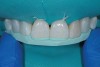

Prior to placing the definitive direct composite restorations on teeth Nos. 8 through 10, the teeth were etched and rinsed, after which adhesive was applied and light-cured (Figure 3). The restoration for tooth No. 10 was layered as previously described.

Fig 3. An adhesive was applied to tooth No. 10 and light-cured.

Figure 3